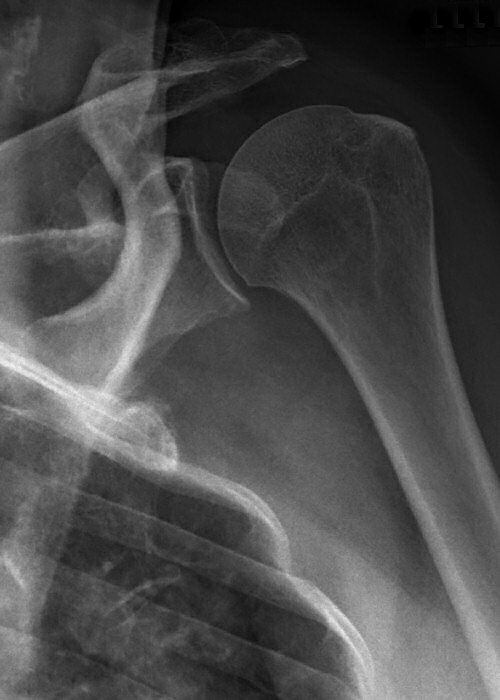

Bakre luxation, patienten hade mycket ont, kunde inte röra axeln alls. På frontalbilden ligger kaput roterat, på sidobild ligger kaput inte rätt i leden, på 3D-rekonstruktion syns felställningen tydligt (delar av nyckelben och akromion bortredigerade).